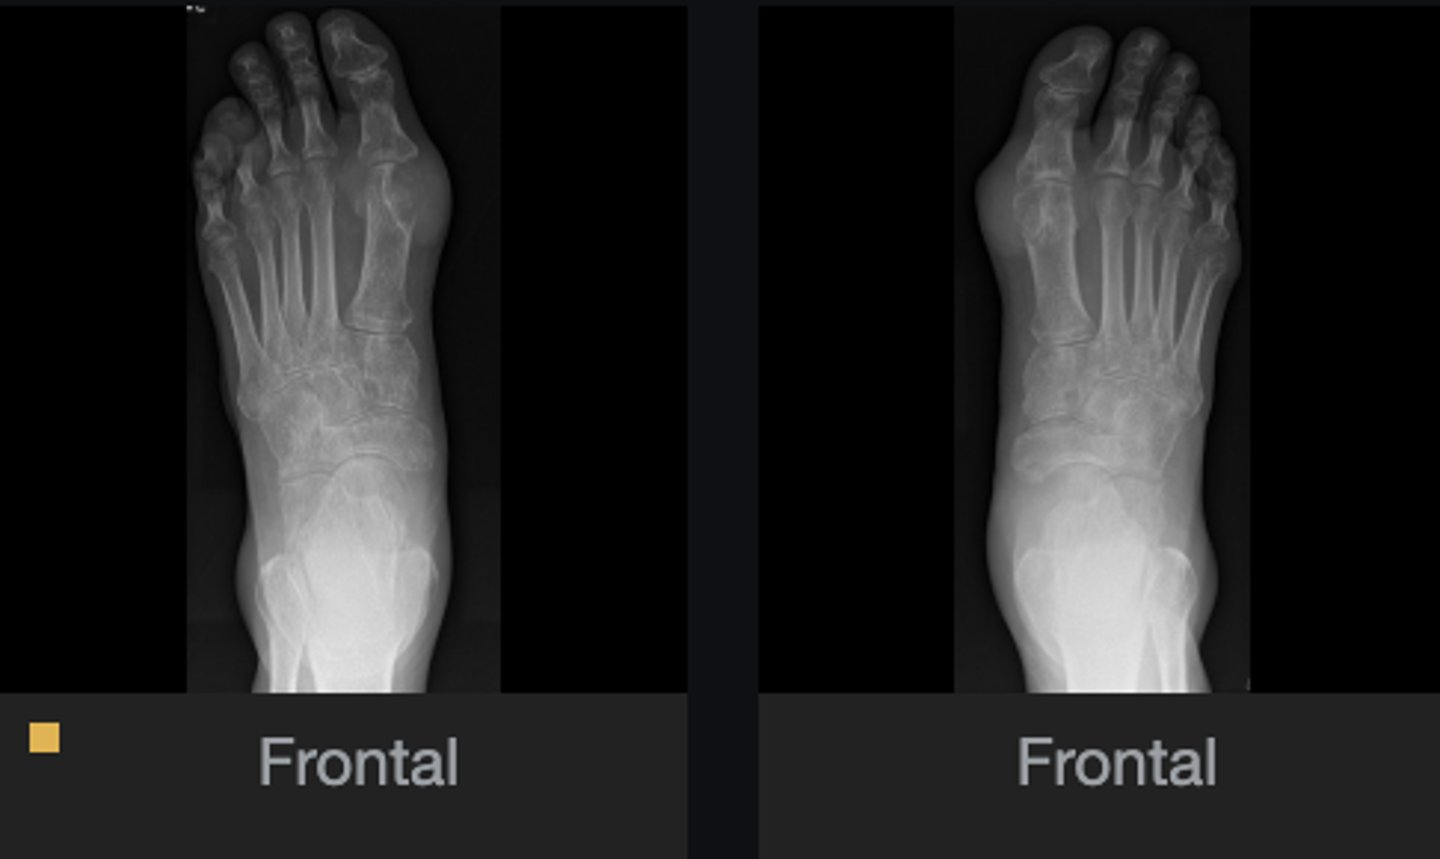

- Erosion of 1st MTP overhanging

- Dense soft tissue swelling around 1st MTP

- 4th/5th digits eroded

What abnormal findings are present on the foot series?

Gout

Diagnosis?